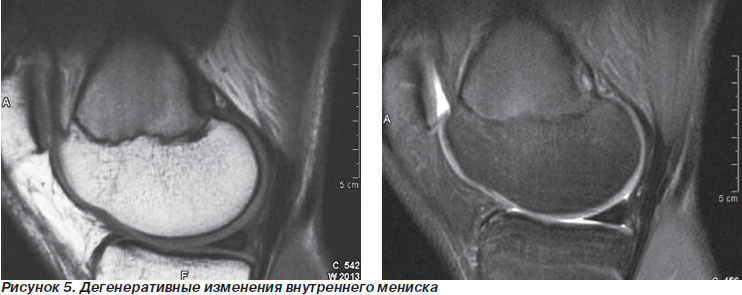

Дегенеративные изменения менисков при анализе МРТ-исследования выявлены у 3 больных. При артроскопии эти изменения не были обнаружены.

Неплохие результаты показала оценка данных МРТ при патологии менисков. Так, например, дегенеративные изменения менисков на начальных стадиях при артроскопии выявить, как правило, не удавалось, в то время как МРТ позволяла их определить.